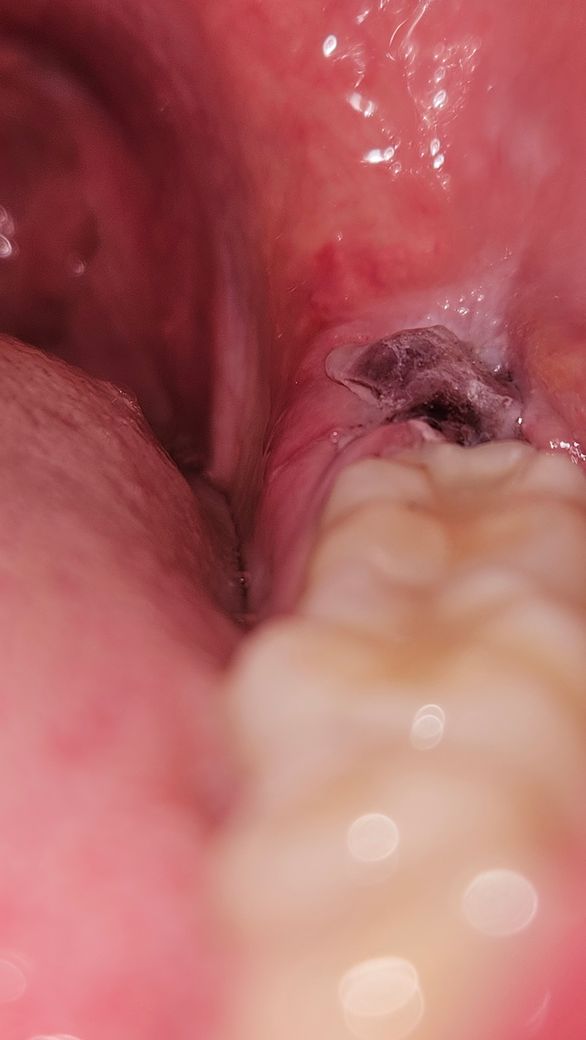

사랑니 발치 후 상태 관련 질문드립니다.

매복 사랑니 월요일에 발치하고 개인사정 때문에 이르게 오늘(목요일) 아침에 실밥을 뽑고왔습니다. 지금 잘 낫고 있는 상태인건가요?

• 2번 째 사진

사진상 문제 될 것은 안보입니다. 추후 통증이 극심해지거나 냄새가 심하게 난다면 치과 가보시면 됩니다.

사진으로만 봤을 경우에는 발치려고 발치한 부위 혈병이 잘 차이는 것으로 보입니다.

혈병에 제거가 되면 치료가 늦어질 수 있기 때문에 해당 부위가 자극되지 않도록 해 주는 것이 좋습니다.

사진상으로 보면 상처가 잘 치유되고 잇습니다. 아직 상처가 다 아문건 아니니 양치를 너무강하게만 하지 마세요.

현재 잘아물고 있는 것으로 보이기에 크게 걱정하지 않으셔도 됩니다.

큰 무리 없이 잇몸 치유가 진행되고 있는 것 같습니다. 다만, 아직까지 완전히 구멍이 메워지지 않았으므로 해당부위로 음식물이 잘 낍니다. 양치질을 살살 해주어 낀 음식물을 잘 빼주시고 그래도 관리가 어렵다면 워터픽이나 주사 시린지로 물을 쏴서 약한 압력으로 음식물을 빼주셔야 합니다.